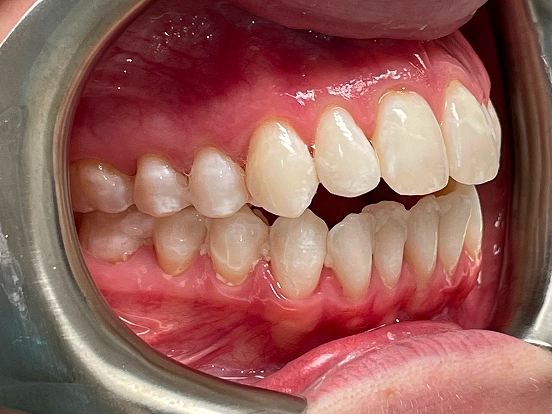

Invisalign DT

DT’s transformation with Invisalign is a perfect example of how advanced orthodontic technology can deliver incredible results. The clear aligners gradually corrected the alignment and bite issues, creating a straighter, healthier, and more attractive smile—all without noticeable brackets or wires.